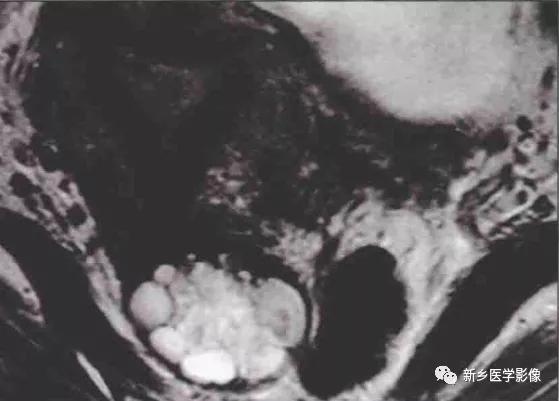

MR表现:表现为宫颈边界清楚的囊性病灶,单发或 多发,单发者多见,通常小于1cm;T1WI:低信号的囊性病灶,少数有黏液成 分表现为高信号3增强后无强化;T2WI:囊肿表现为高信号,如含有黏液蛋 白则信号低于单纯囊肿